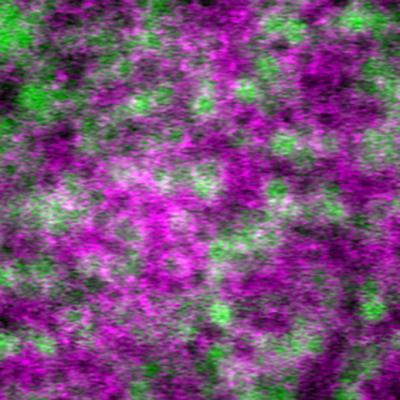

Multimodal image of retinal pigment epithelial cells.

Multimodal image of retinal pigment epithelial cells. Image generated using a combination of four adaptive optics imaging modalities (magenta = summation of adaptive optics optical coherence tomography, adaptive optics infrared autofluorescence, and darkfield; green = late phase adaptive optics indocyanine green image). Individual cells labeled by indocyanine green are contained within cell outlines visualized using complementary techniques.

Read the associated publication